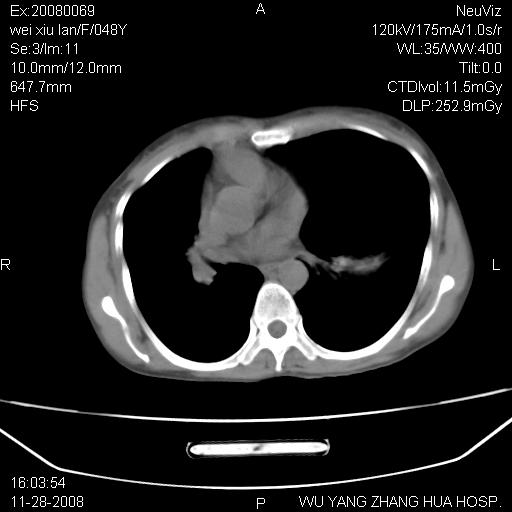

标题: CT16847:女,48岁,咳嗽,发热两日,平常偶有上腹部不适。 [打印本页]

标题: CT16847:女,48岁,咳嗽,发热两日,平常偶有上腹部不适。

能否考虑食管裂孔疝?请老师们多多指教。

这个是左侧膈膨升伴不完全性胃翻转,手术将松弛的左横膈膜折叠缝合即解决问题。

支持左侧膈疝,心脏受压右移.

胃、脾脏及部分肠管明显升高,并压迫心脏移位,

首先考虑:左侧膈疝。

左侧胸腔内见胃肠及脾脏影

支持膈疝

左下肺不张、膈膨升,胸腔胃